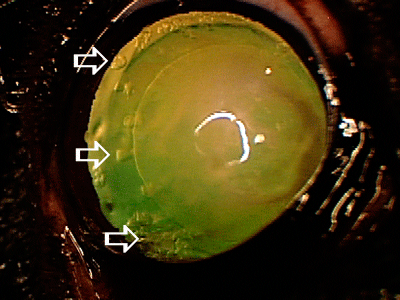

Early cataracts (white arrows). These early cataracts do not interfere with vision, however rapid progression of cataracts is possible, which may result in vision loss and different ocular complications. Regular monitoring of cataract progression should be pursued with your local veterinarian.

Early cataracts (white arrows). These early cataracts do not interfere with vision, however rapid progression of cataracts is possible, which may result in vision loss and different ocular complications. Regular monitoring of cataract progression should be pursued with your local veterinarian.